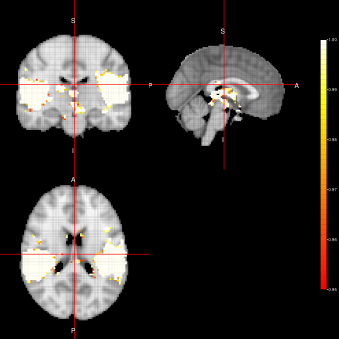

From figures 2, 3 and 4, we can see the activation maps obtained for the ”voice localizer” experiment using the method proposed in this work. From those images, we can say that the three algorithms (FEST, FFBS and FSTS) under the three different distributions (Marginal, joint and LTT or average distribution) successfully identify the temporal activation due to voice and non-voice sounds stimulation, nevertheless there are some slight differences among those maps worth mentioning. For instance, the maps obtained when using the FFBS algortihm allows for the identification of a broader activated region from the temporal cortex, however, on the other hand, it allows activations to appear (false-positive activations) on brain regions that should not be involved with this ”voice localizer” experiment. On the other hand, more conservative results seem to be obtained when using FEST and FSTS algorithms, but with less false activations.

Marginal-FSTS Joint-FSTS

Refer to caption Refer to caption

ACE-FSTS

Refer to caption

Figure 4: Activation Maps obtained for the ”voice localizer” example when using the FSTS algorithm under three different distributions (Marginal, Joint and LTT) related to the state parameter.